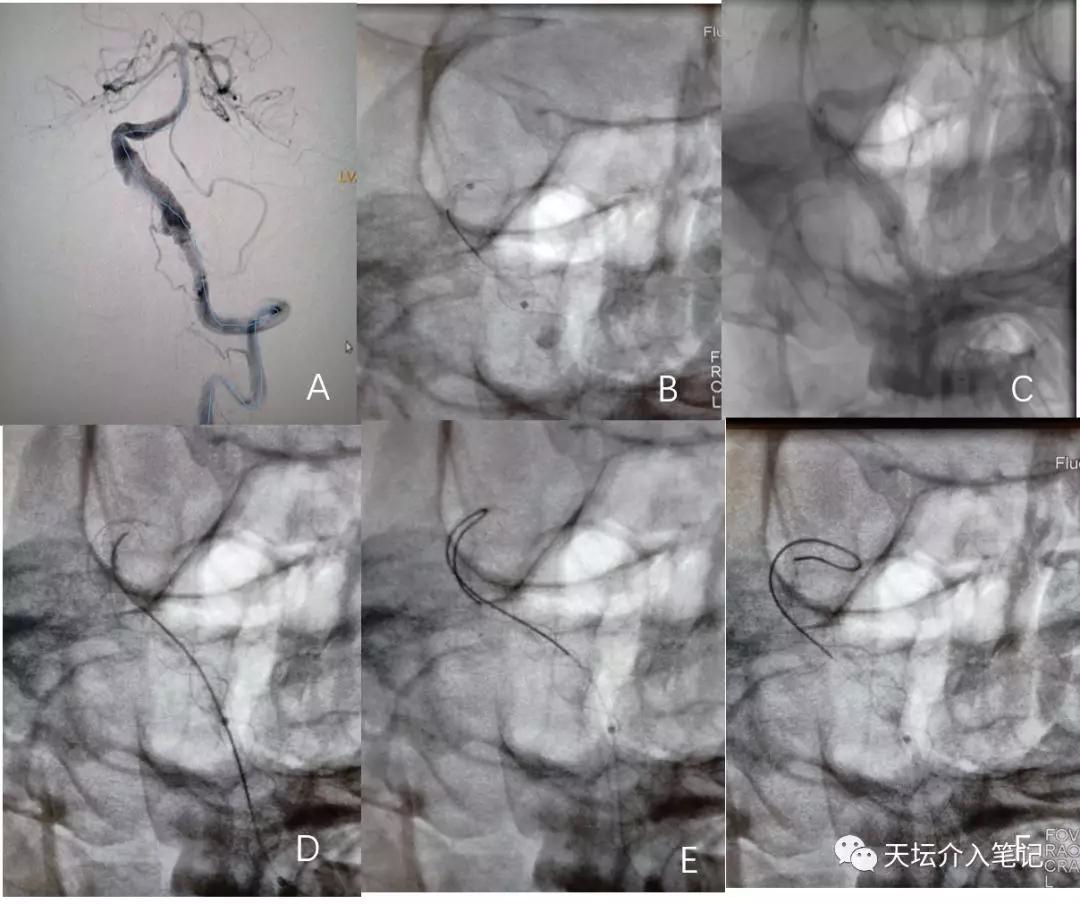

图 3

A.T-TRACK支架管到位;B.Tubridge® 6.5×45mm支架释放;C.支架术后造影,远端打开不良;DEF.应用微导丝成攀技术对支架进行按摩

术后性DynaCT检查示支架到位打开良好(图4)。